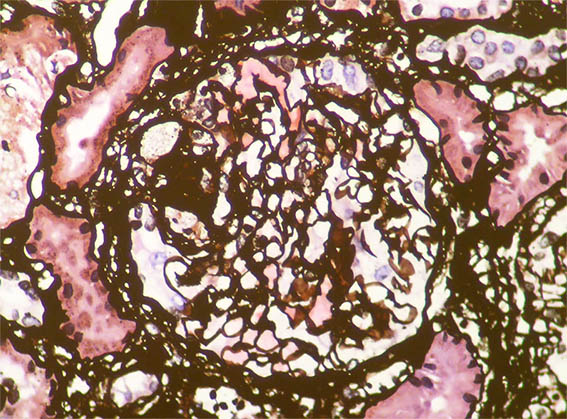

Figure 4. Methenamine-silver stain, X400.